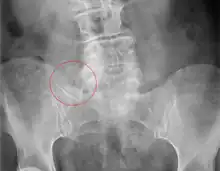

| X-ray of Bertolotti's syndrome (in this case, right transverse mega-apophysis of L5 with pseudoarticulation with the sacral ala). Woman 67 years old. |

Bertolotti's syndrome is a commonly missed cause of back pain which occurs due to lumbosacral transitional vertebrae (LSTV). It is a congenital condition but is not usually symptomatic until one's later twenties or early thirties.[1] However, there are a few cases of Bertolotti's that become symptomatic at a much earlier age.

Bertolotti's syndrome is characterized by sacralization of the lowest lumbar vertebral body and lumbarization of the uppermost sacral segment. It involves a total or partial unilateral or bilateral fusion of the transverse process of the lowest lumbar vertebra to the sacrum, leading to the formation of a transitional 5th lumbar vertebra. Of importance is that this syndrome will result in a pain generating 4th lumbar disc resulting in a "sciatic" type of a pain correlating to the 5th lumbar nerve root. Usually the transitional vertebra will have a "spatulated" transverse process on one side resulting in articulation or partial articulation with the sacrum or at time the ilium and in some cases with both. This results in limited / altered motion at the lumbo-sacral articulation. This loss of motion will then be compensated for at segments superior to the transitional vertebra resulting in accelerated degeneration and strain through the L4 disc level which can become symptomatic and inflame the adjacent L5 nerve root resulting in "sciatic" or radicular pain patterns. Scoliosis is frequently found to be associated.[4]